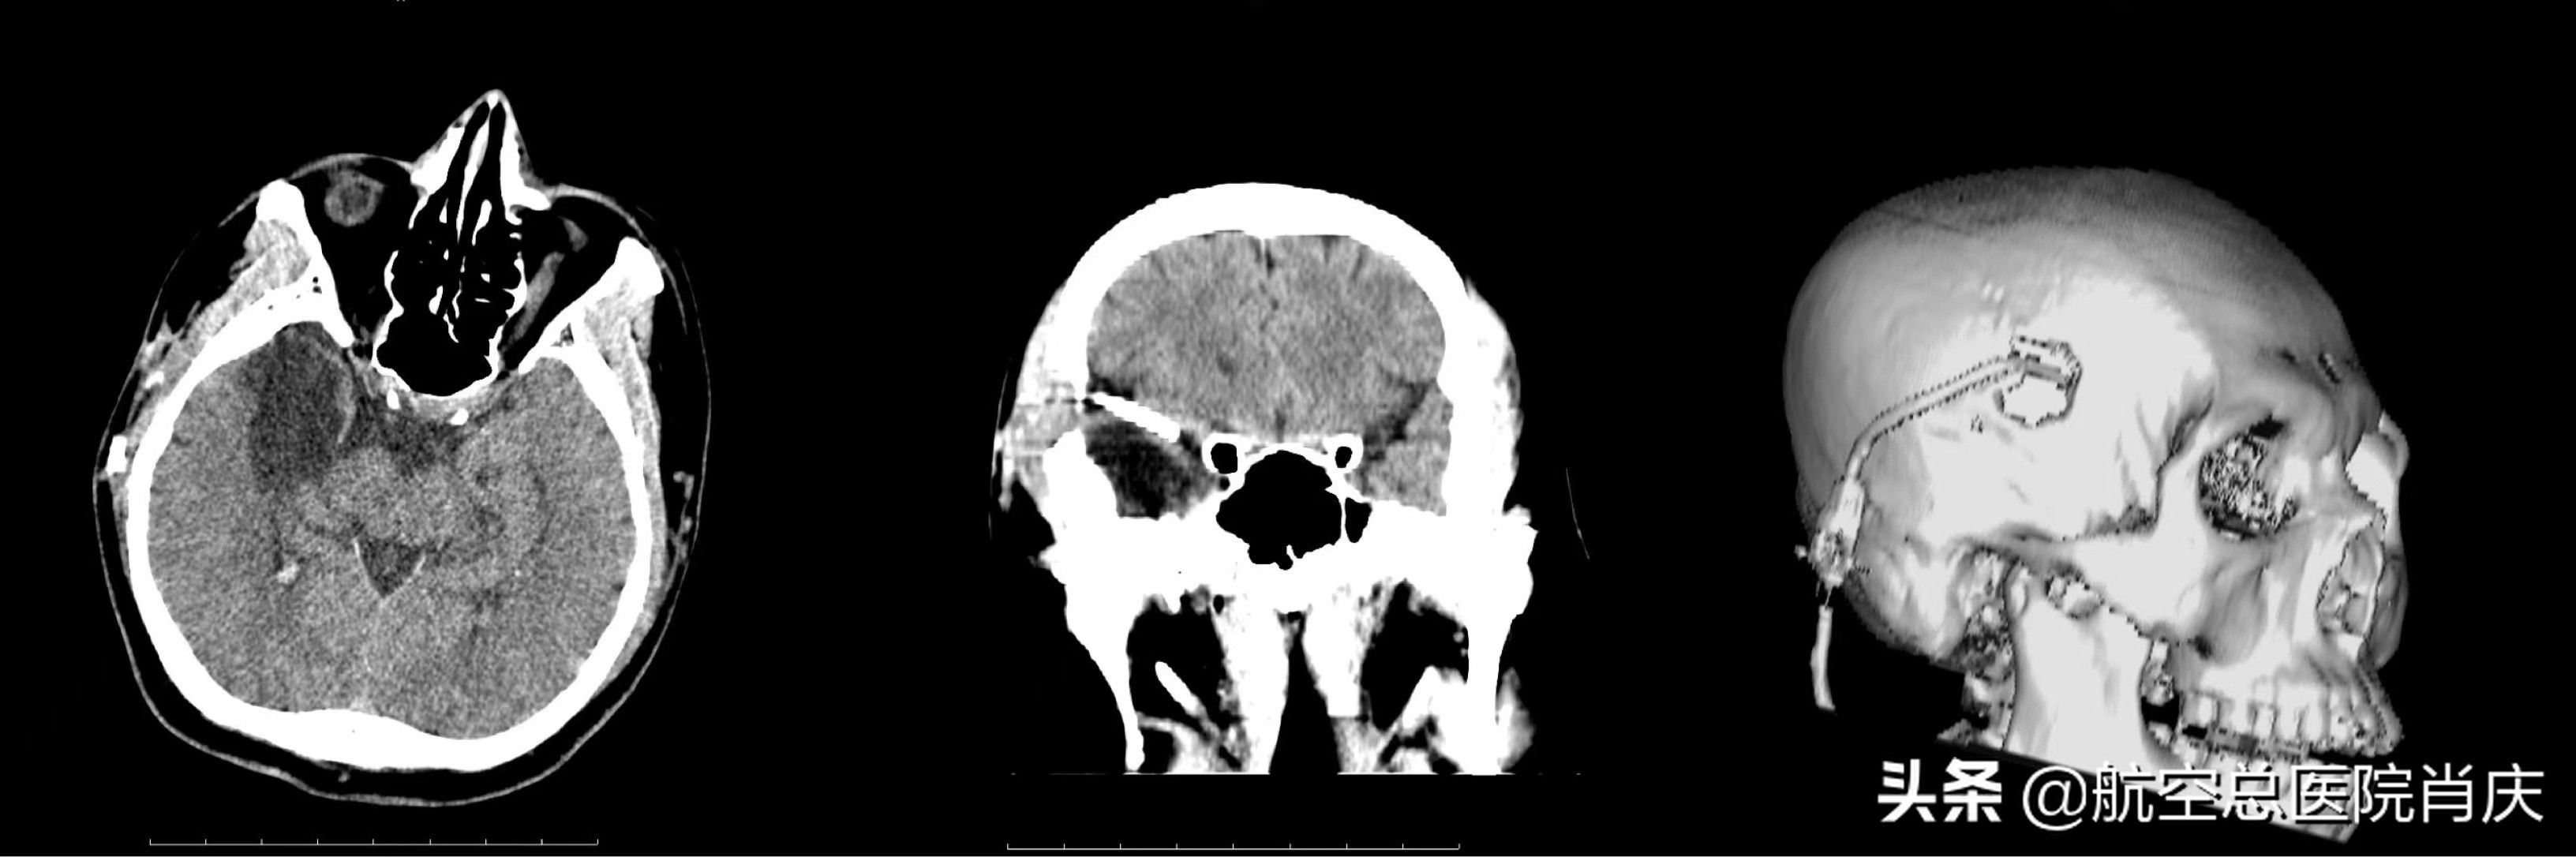

术前

鲁先生入院后完善各项检查,肖庆主任团队详细了解患者病史,并根据患者的个人情况制定了个性化治疗方案。虽然患者从小便经历了大小手术,但作为患者的母亲依然紧张万分,肖庆主任耐心与患者和家属沟通,讲解治疗方案,安抚他们焦虑紧张的心情,使患者可以在一个平和的情绪环境中进行接下来的治疗。